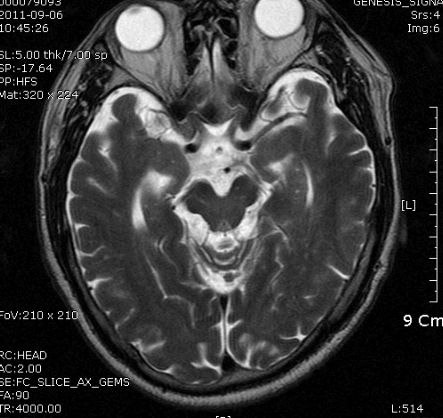

B MRI 촬영 결과는 좌측의 corona radiata, Lt temporo-occipital lobe 의 subcortical area 의 optic radiation 부위를 비롯한 여러 군데 점상 병변. N/S 정주하고 Aspirin 투여 시작, 혈압약은 지속 투여, SBP 160정도로 유지.

촬영 결과는 좌측의 corona radiata, Lt temporal lobe는 anterior choroidal artery 영역입니다.

Anterior choroidal과 posterior choroidal artery의 영역을 공유하는 경우가 있는 것 같습니다. anterior choroidal 막히면 poster choroidal artery 가 대신 혈액공급을 담당하는 경우가 있습 것 같습니다.

두 혈관은 서로 collateral 있습니다. 그러므로 한쪽이 hypoplasia나 chronic stenosis 있다면 PChA가  AChA 영역을 보충할 수 있는 것 같습니다. (Sohn's theory).  이환자에서 anterior choroidal artery가 서서히 막혀서 posterior choroidal artery가 대신 그 역활을 하고 있는데  left PCA 영역에  A to A가 생겼다면 가능......

좌측사진은 PCA 영역. 우측사진은  AchA 영역의 post. periventricular corona radiata (Stroke 4ed p199, Fig 9-3 과 동일)